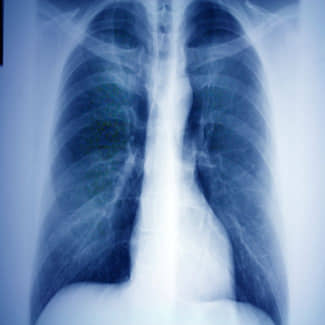

De kwaliteit van leven van patiënten met chronische longaandoeningen als astma, COPD en longkanker kan en moet beter. Het Nederlandse consortium Precisie geneeskunde voor meer zuurstof (P4O2) gaat daarom onderzoek doen naar fundamentele verbeteringen in preventie en behandeling van longziekten.

Onderzoekers van de afdeling Longziekten in het LUMC richten zich binnen het consortium op het ontwikkelen van een nieuw celkweekmodel. Hierbij proberen ze de complexe omgeving van schade aan longblaasjes (emfyseem) goed na te bootsen. Deze zogenoemde Long-Chip modellen maken gebruik van uit stamcellen verkregen longcellen. Deze cellen worden ingezet om biomarkers en farmacologische therapiestrategieën te identificeren en te valideren die binnen het consortium worden toegepast.

“Het is een ongelofelijke spannende uitdaging om op microniveau longblaasjes na te bootsen in het laboratorium. Dat doen we met een model waarbij ook de effecten van ademhaling op de longblaasjes zo goed mogelijk worden nagebootst”, vertelt onderzoeker Anne van der Does. “We verwachten zo weer een stap dichterbij te komen tot een betere vertaling van het onderzoek naar de longen van onze patiënten.”

Binnen de eerder aangekondigde COVID-19 extensie van het project is de kliniek van de afdeling Longziekten betrokken bij het in kaart brengen van mogelijke longschade specifiek gericht op COVID-19 patiënten.